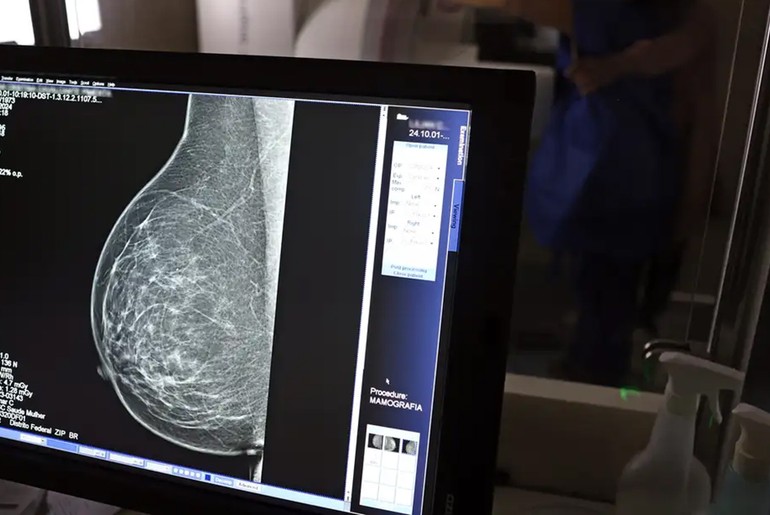

Foi publicada no Diário Oficial da União, uma Lei que fortalece o acesso das mulheres ao exame de mamografia fornecido pelo Sistema Único de Saúde (SUS). A partir de agora, o procedimento é garantido a mulheres a partir dos 40 anos de idade. Anteriormente, a idade em que o atendimento era oferecido, salvo casos especiais, era 50 anos.

A garantia ao exame se dará mesmo que as mulheres não apresentem sinais ou sintomas de câncer. A faixa etária dos 40 aos 49 anos concentra 23% dos casos da doença e a detecção precoce aumenta as chances de cura.

A recomendação para as mulheres a partir dos 40 anos é que o exame de mamografia seja feito sob demanda, em decisão com o profissional de saúde. A paciente deve ser orientada sobre os benefícios e desvantagens de fazer o rastreamento.

Mulheres nesta idade tinham dificuldade com o exame na rede pública de saúde em função da avaliação de histórico familiar ou necessidade de já apresentar sintomas. Apesar disso, as mamografias no SUS em pacientes com menos de 50 anos representam 30% do total, equivalente a mais de 1 milhão em 2024.